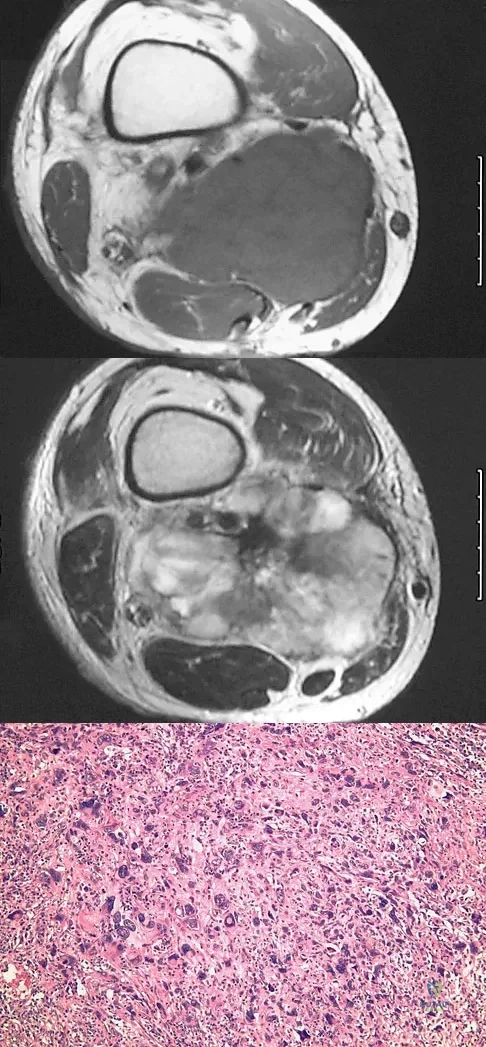

A healthy 16-year-old boy has had increasing pain in the right knee for the past 3 months. Examination reveals warmth and swelling around the distal femur. Radiographs and an MRI scan are shown in Figures 51a through 51c, and a biopsy specimen is shown in Figure 51d. What is the most likely diagnosis?

Explanation